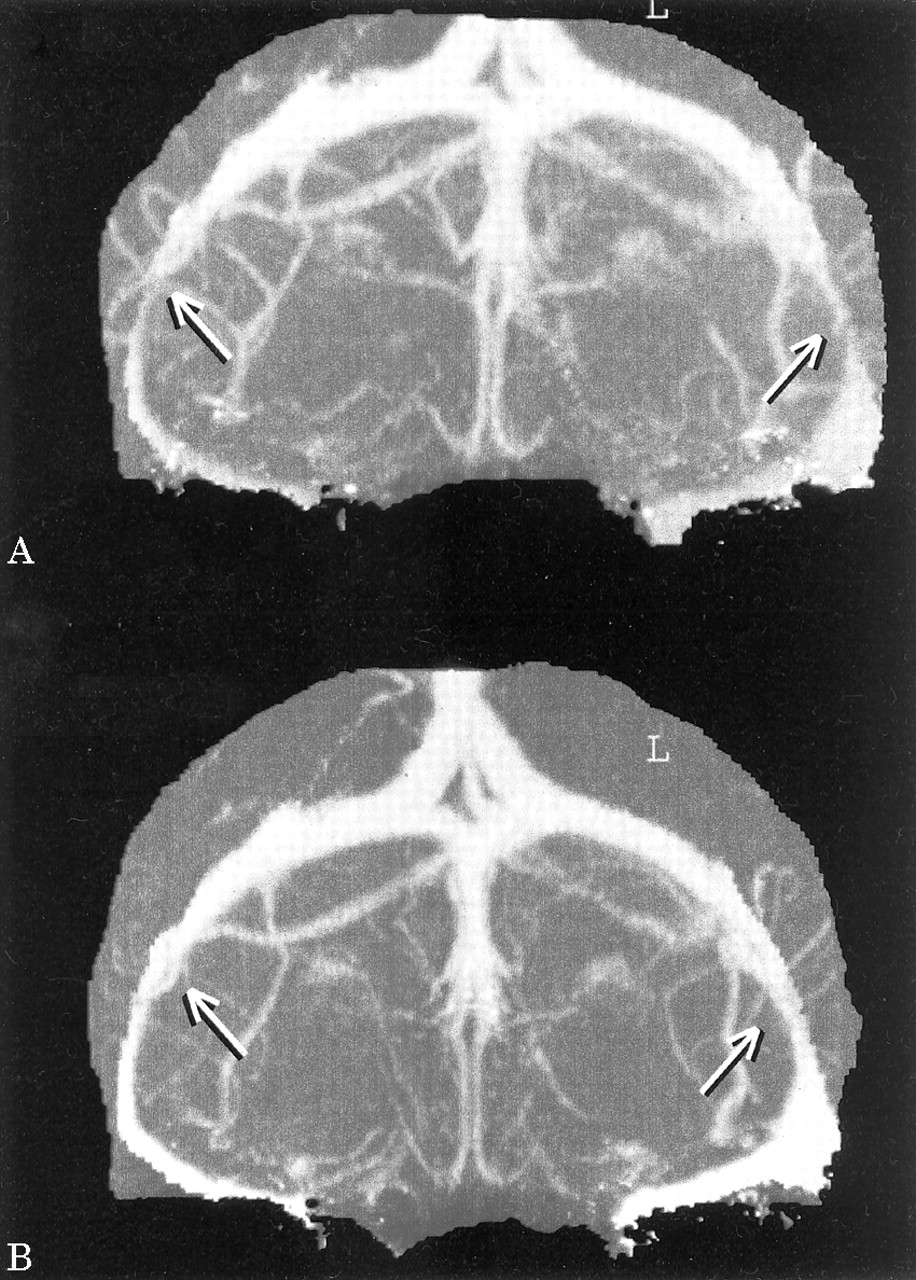

Unenhanced CT和MRI的大脑是正常的。腰椎穿刺入学当天透露CSF开启压力的升高67厘米(正常< 20)与正常脑脊液成分。CT静脉造影术执行第二天显示严重狭窄的远端横向鼻窦与没有证据表明颅内静脉窦血栓形成(图,一个)。3电解质、钙含量和全血计数是正常的。

CT静脉造影照片重复了6天后并联插入和显示显著减少横窦的程度缩小双边(图B)。病人出院不头痛的改善视觉功能(VA 6/9和6/12左右)。